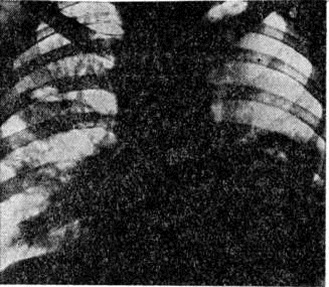

Лимфатических, узлы обычно увеличены незначительно, между собой не спаяны, эластической консистенции, серо-розового цвета, иногда с мелкоточечными кровоизлияниями. В некоторых случаях выявляется увеличение миндалин, лимфатических, фолликулов и пейеровых бляшек с наличием очаговых некрозов и изъязвлений, однако такие изменения встречаются значительно реже, чем при острых Лейкозы. Лёгкие нередко увеличены в объёме, сероватого цвета, под плеврой и в толще лёгочной ткани определяется мелкопетлистая сеть сосудов, часто встречаются участки пневмонии.

При микроскопическом исследовании в костном мозге преобладают незрелые и зрелые клетки гранулоцитарного ряда (рисунок 5), соотношение которых может варьировать. По данным трепанобиопсий, в начальной стадии заболевания ещё в достаточном количестве сохраняются элементы эритропоэтического и мегакариоцитарного ряда. По мере прогрессирования процесса их число снижается, исчезают жировые клетки. Характерны глубокие изменения в строме в виде сочетания процессов деструкции с увеличением количества фибробластов, аргирофильных и иногда коллагеновых волокон. Изучение костного мозга методом трепанобиопсии в динамике свидетельствует о том, что миелофиброз постепенно нарастает и бывает более выражен у больных с повторными ремиссиями и обострениями заболевания. В отдельных случаях в костном мозге имеют место обширные очаги некроза; постоянно наблюдается выраженное рассасывание костной ткани. В селезёнке и лимфатических узлах в развёрнутой стадии болезни обнаруживается диффузная инфильтрация миелоидными элементами, атрофия лимфатической ткани. Лейкозное поражение селезёнки часто сопровождается выраженным в различной степени фиброзом красной пульпы, образованием полей склероза, что наряду с инфильтрацией и полнокровием является причиной увеличения её веса. Для хронический миелолейкоза характерна локализация лейкозных инфильтратов в печени по ходу синусоидных капилляров (рисунок 6), в лёгких — в области межальвеолярных перегородок. Нередко наблюдается инфильтрация стенок мелких бронхов, сосудов, плевры. Реже, чем при острых Лейкозы очаги лейкозной инфильтрации возникают в почках, мышце сердца, в стенках желудочно-кишечные тракта, в оболочках и веществе головного мозга, коже, железах внутренней секреции и других органах.